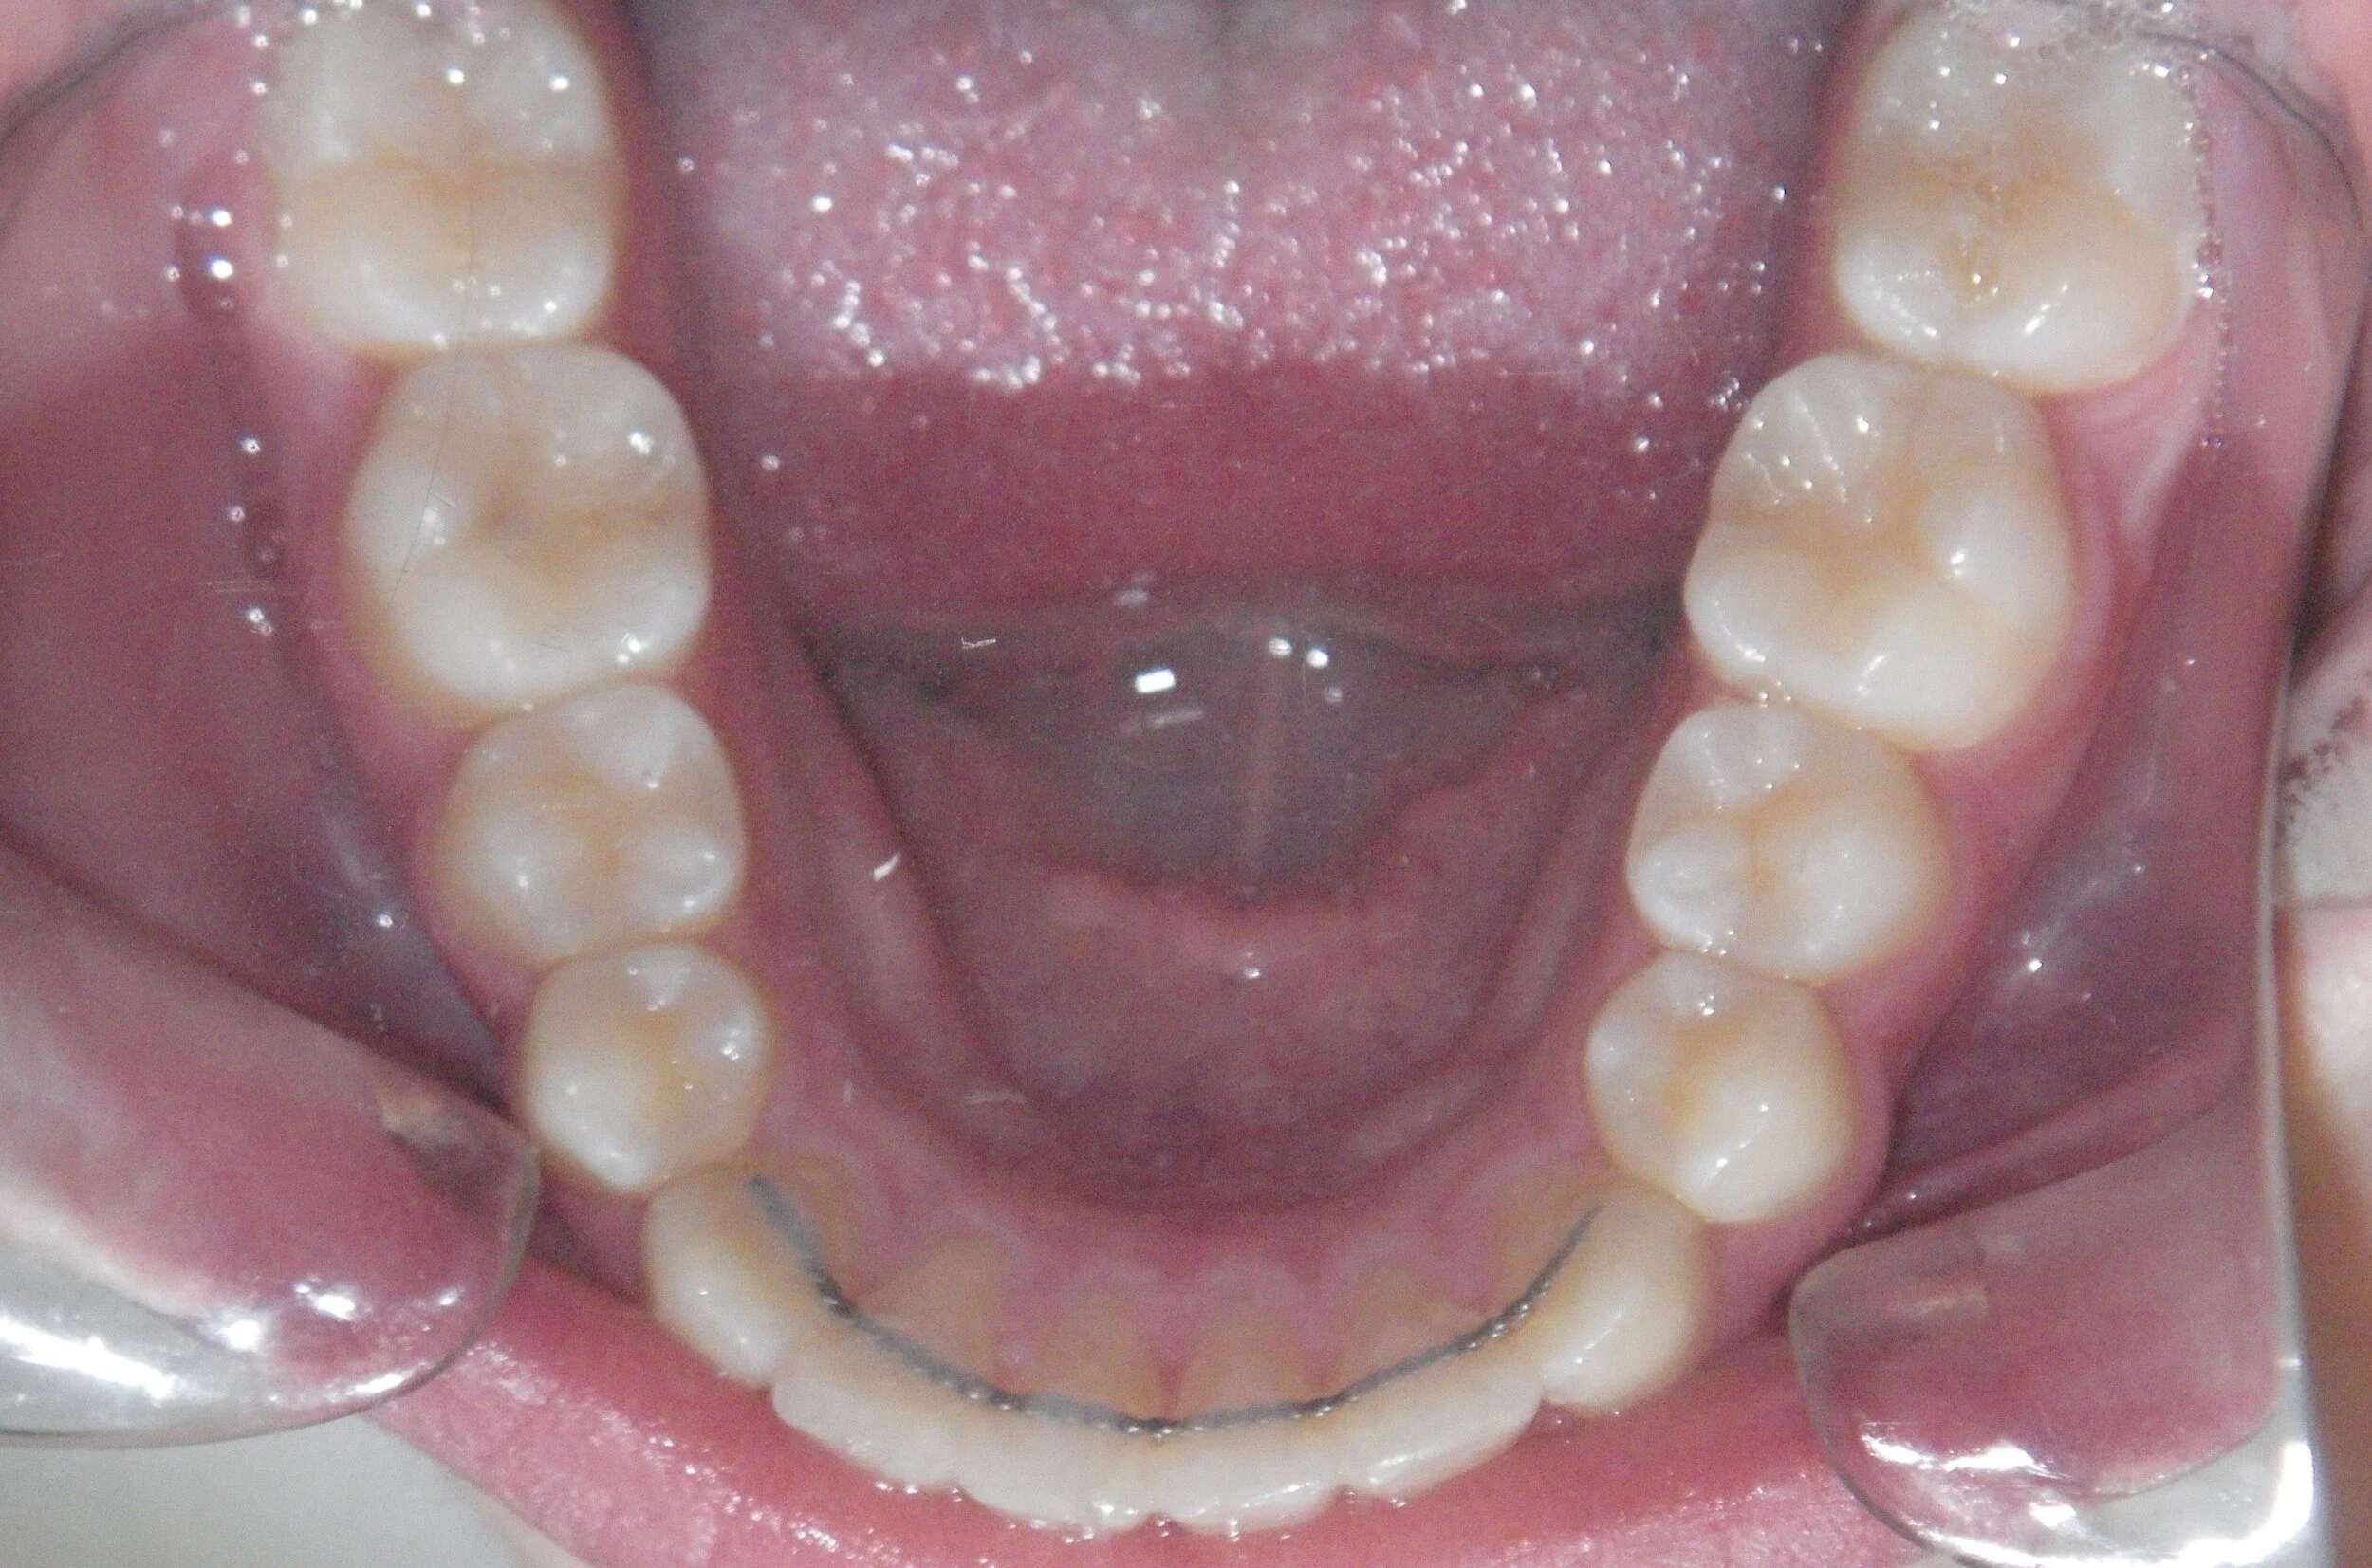

Phase I can be used to help change unfavorable growth or to make room so all the adult teeth have room to erupt. Here, we used Phase I to make room for the adult canines and followed up with Phase II treatment to a get a great esthetic and functional result!